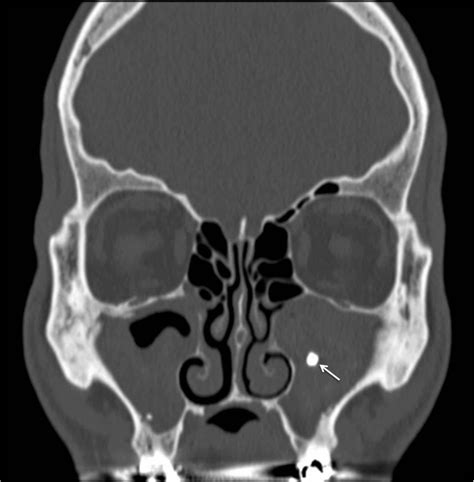

• Fungal Ball (Mycetoma): This is a non-invasive form where a dense accumulation of fungal hyphae develops in a single sinus cavity, usually the maxillary sinus. It often occurs in individuals with normal immune systems and is usually cleared through surgical removal.

Imaging (CT Scan) Mucosal thickening High-density spots or calcifications

• Computed Tomography (CT) Scan: This imaging provides a detailed view of the sinuses and can highlight calcifications or specific patterns characteristic of fungal growth.